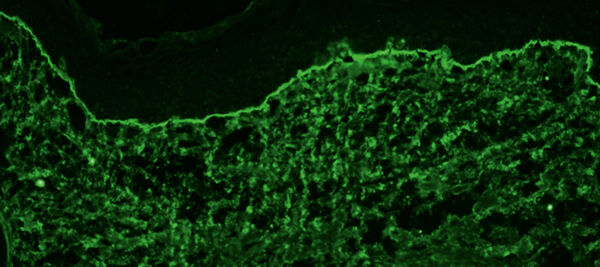

Die direkte Immunfluoreszenz zeigt charakteristischerweise lineare Ablagerung von Immun­globulinen und/oder Komplement (C3) an der dermoepidermalen Junktionszone. Die Serumspiegel der Autoantikörper gegen Kollagen VII korrelieren gut mit der klinischen Erkrankungs­aktivität. Daher eignet sich die Bestimmung dieser Autoantikörper mittels quantitativer Immuno­assays (ELISA) auch als Verlaufsparameter.

Direkte Immunfluoreszenz einer periläsionalen Hautbiopsie beim bullösen Pemphigoid zeigt Ablagerungen von Komple­ment C3 an der dermoepidermalen Junktionszone (x 250).